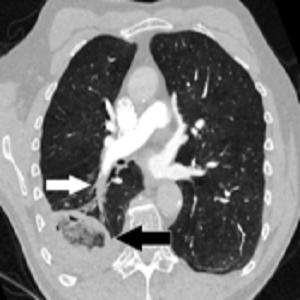

Pulmonary embolism (PE) is a blockage of an artery in the lungs by a substance that has moved from elsewhere in the body through the bloodstream (embolism). Symptoms of a PE may include shortness of breath, chest pain particularly upon breathing in, and coughing up blood.Symptoms of a blood clot in the leg may also be present, such as a red, warm, swollen, and painful leg.<br />PE usually results from a blood clot in the leg that travels to the lung. The risk of blood clots is increased by advanced age, cancer, prolonged bed rest and immobilization, smoking, stroke, long-haul travel over 4 hours, certain genetic conditions, estrogen-based medication, pregnancy, obesity, trauma or bone fracture, and after some types of surgery. A small proportion of cases are due to the embolization of air, fat, or amniotic fluid.<br />Diagnosis is based on signs and symptoms in combination with test results. If the risk is low, a blood test known as a D-dimer may rule out the condition.Otherwise, a CT pulmonary angiography, lung ventilation/perfusion scan, or ultrasound of the legs may confirm the diagnosis. Together, deep vein thrombosis and PE are known as venous thromboembolism (VTE).<br />Management <br />Efforts to prevent PE include beginning to move as soon as possible after surgery, lower leg exercises during periods of sitting, and the use of blood thinners after some types of surgery. Treatment is with anticoagulants such as heparin, warfarin or one of the direct-acting oral anticoagulants (DOACs). These are recommended for at least three months. Severe cases may require thrombolysis using medication such as tissue plasminogen activator (tPA) given intravenously or through a catheter, and some may require surgery (a pulmonary thrombectomy). If blood thinners are not appropriate, a temporary vena cava filter may be used.<br /><br />